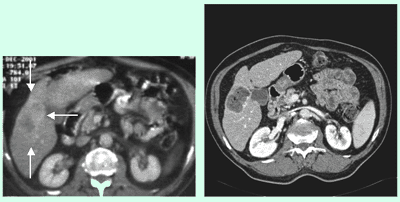

Die Abdomensonographie ist als Screeninguntersuchung und für eine routinemäßige Verlaufskontrolle bei Aneurysmen gut geeignet. Zur exakten Bestimmung der Größe und Morphologie wird jedoch eine Computertomographie (Abb. 1), in Ausnahmefällen eine Magnetresonanztomographie, durchgeführt.

Alternativ zur offenen chirurgischen Therapie eines Aortenaneurysmas besteht die Möglichkeit einer endovaskulären Aneurysmaausschaltung mittels eines Stentgrafts (gewebeummanteltes Metallgittergeflecht). Voraussetzung für die endovaskuläre Therapie ist jedoch eine anatomische Eignung, welche eine ausreichende Weite der Beckengefäße und nötige Verankerungszonen für den Stentgraft mit sich bringt. Die Stentgraft Implantation wird von Interventionellen Radiologen in Zusammenarbeit mit Anästhesist:innen und Gefäßchirurg:innen durchgeführt. Der Eingriff erfolgt unter Spinalanästhesie oder einer Allgemeinnarkose. Der Zugang zum Aneurysma wird üblicherweise durch einen kurzen Schnitt in der Leiste geschaffen. Zur Darstellung des Aneurysmas wird zuerst eine Angiographie der Bauchaorta durchgeführt (Abb.2). Folglich wird unter Röntgendurchleuchtung der Stentgraft über einen Führungsdraht in die Bauchaorta eingebracht und unterhalb der Nierenarterien verankert. Eine Kontrollangiographie nach Stentgraft-Implantation wird zum Nachweis eines guten Ausschlusses des Aneurysmas durchgeführt (Abb.3).

© Universitätsklinik für Radiologie und Nuklearmedizin

Abbildung:

Die Abbildung zeigt eine CT Angiographie der abdominellen Aorta bei einem 85-jährigen Patienten. Die CTA zeigt ein Aneurysma der Aorta. Aufgrund des geringen Abstandes vom Beginn des Aneurysmas zu den akzessorischen Nierenarterien ist eine Behandlung des Aneurysmas mittels Stentgraftimplantation nicht möglich.